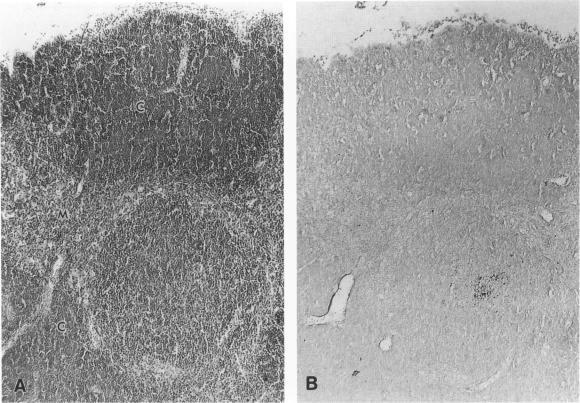

The distribution and sequential development of prion protein (PrP) accumulation in the central nervous system (CNS) and non-neuronal organs of mice infected with Creutzfeldt-Jakob disease (CJD) were investigated immunohistochemically using a new pretreatment method that greatly enhanced the immunoreactivity of PrP. Prion protein accumulation in the CNS was first detected at 30 days after inoculation and then developed near the inoculation site or periventricular area, and later spread to the whole cerebrum and then to the pons. Its staining took some characteristic forms. Among non-neuronal organs, PrP accumulated in the follicular dendritic cells (FDCs) in spleen, lymph node, Peyer's patch, and thymus. FDCs staining appeared in spleen, lymph node, and Peyer's patch at 21 or 30 days after inoculation, and in thymus at 90 days. Germinal centers developed in the thymus of some CJD-infected mice. No PrP staining was detected in any examined organs of age-matched control mice.

采用一种能显著增强朊病毒蛋白(PrP)免疫反应性的新预处理方法,通过免疫组织化学研究了感染克雅氏病(CJD)的小鼠中枢神经系统(CNS)和非神经器官中PrP积累的分布及顺序发展情况。接种后30天首次在CNS中检测到PrP积累,随后在接种部位附近或脑室周围区域出现,之后扩散至整个大脑,再到脑桥。其染色呈现出一些特征性形态。在非神经器官中,PrP在脾脏、淋巴结、派伊尔结和胸腺的滤泡树突状细胞(FDCs)中积累。接种后21天或30天,脾脏、淋巴结和派伊尔结出现FDCs染色,90天胸腺出现染色。一些感染CJD的小鼠胸腺中出现生发中心。在年龄匹配的对照小鼠的任何检测器官中均未检测到PrP染色。